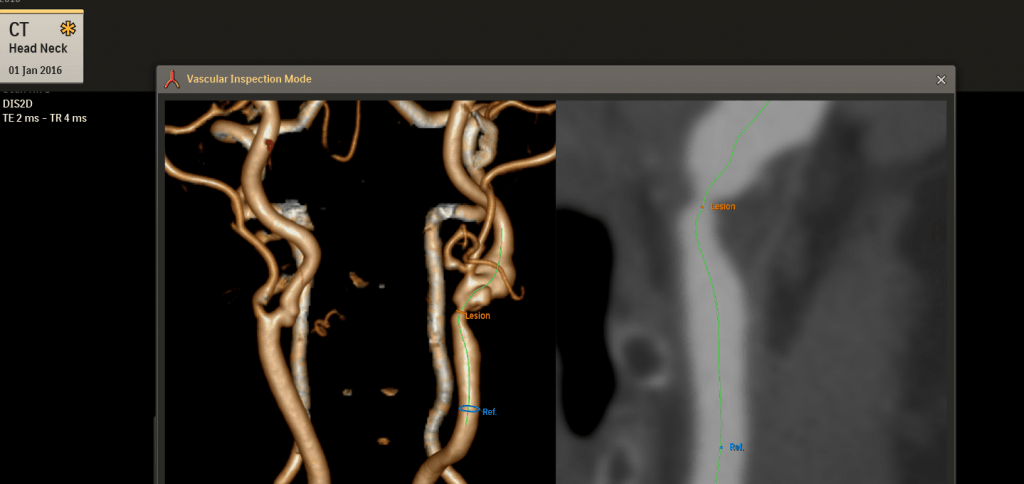

En het bedrijf lanceert een nieuw systeem voor radiologie, Illumeo. Die technologie noemt Jeroen Tas een ‘volgende generatie user interface voor radiologen’. “Illumeo is een beeldgestuurde technologie voor radiologen, die zich automatisch aanpast aan voorkeuren van de gebruiker, relevante informatie verzamelt en de context van de patiënt presenteert”, aldus Jeroen Tas. Philips verwerkte in Illumeo een patient briefing, gebaseerd op de mission briefing die je bij games vooraf krijgt. “Die patient briefing bevat alle relevante informatie van een patiënt: niet alleen de MRI-scan, maar ook eerdere beelden en de context van de patiënt”, aldus Tas.

Inzoomen op een CT-scan en bloedvat met Illumeo